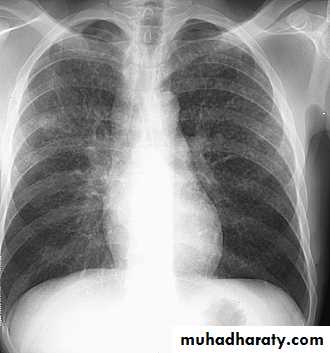

• Pleural effusion : collection of fluid within the pleural space. This can be further divided into Transudate , exudate, according to protein content .Other type of fluid collection within pleural space are

• Chest x-rays are the most commonly used examination to assess for presence of a pleural effusion, however it should be noted that on a routine erect frontal chest x-ray as much as 200-500 ml of fluid is

• required before it becomes evident .

blunting of the costophrenic angle

blunting of the cardiophrenic angle

fluid within the horizontal or oblique fissures

eventually a meniscus will be seen, on frontal films seen laterally and gently sloping medially

with large volume effusions, mediastinal shift occurs away from the effusion

• Lateral films are able to identify a smaller amount of fluid ( about75%)as the costophrenic angles are deepest posteriorly posteriorly

Pleura effusion signs

Obliteration of costo-pherinic anglesMeniscus sign

Lenticular sign